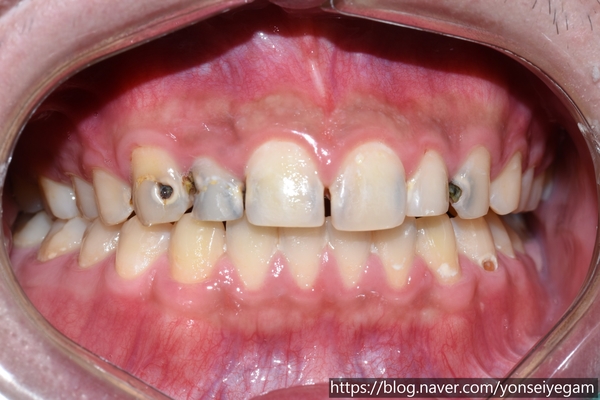

앞에서 봤을 때도 충치가 심해 보였고, 특히 앞니 충치가 눈에 띄게 보였습니다.

그런데 속(입천장)쪽에서 거울을 대고 봤을 때는 앞에서 봤을 때보다도 더 충치가 심각함을 알 수 있습니다.

이렇게 앞니 까지 다 썩어있는 경우는 보통 <1. 비용문제 때문에> 또는 <2. 치과치료를 극도로 무서워 해서> 치과치료를 미루다 보니 이렇게 썩게 되는 경우가 많은데 불과 몇 년전에 치아교정을 했다니! 놀라울 따름 이었습니다.

윗니의 경우 치아 입천장쪽을 보면 충치가 아주 심한 것을 볼 수 있습니다.